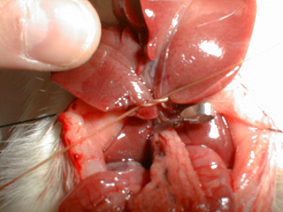

Isquemia hepática

| 1 | Puesta a punto de un modelo experimental para el estudio de la isquemia hepática normotérmica |

| XXV

Congreso Nacional de la Asoc. Esp. para el estudio del Hígado.

Madrid, 2.000. Desarrollo de un modelo de isquemia hepática

intermitente con hepatectomía en la rata. C. Loureiro, I. García-Alonso,

V. Portugal.

XI Congreso de la Asoc. Esp. de Investigaciones Quirúrgicas. Bilbao, 2.000. Desarrollo de un modelo de isquemia hepática intermitente con hepatectomía en la rata. C. Loureiro, I. García-Alonso, V. Portugal.